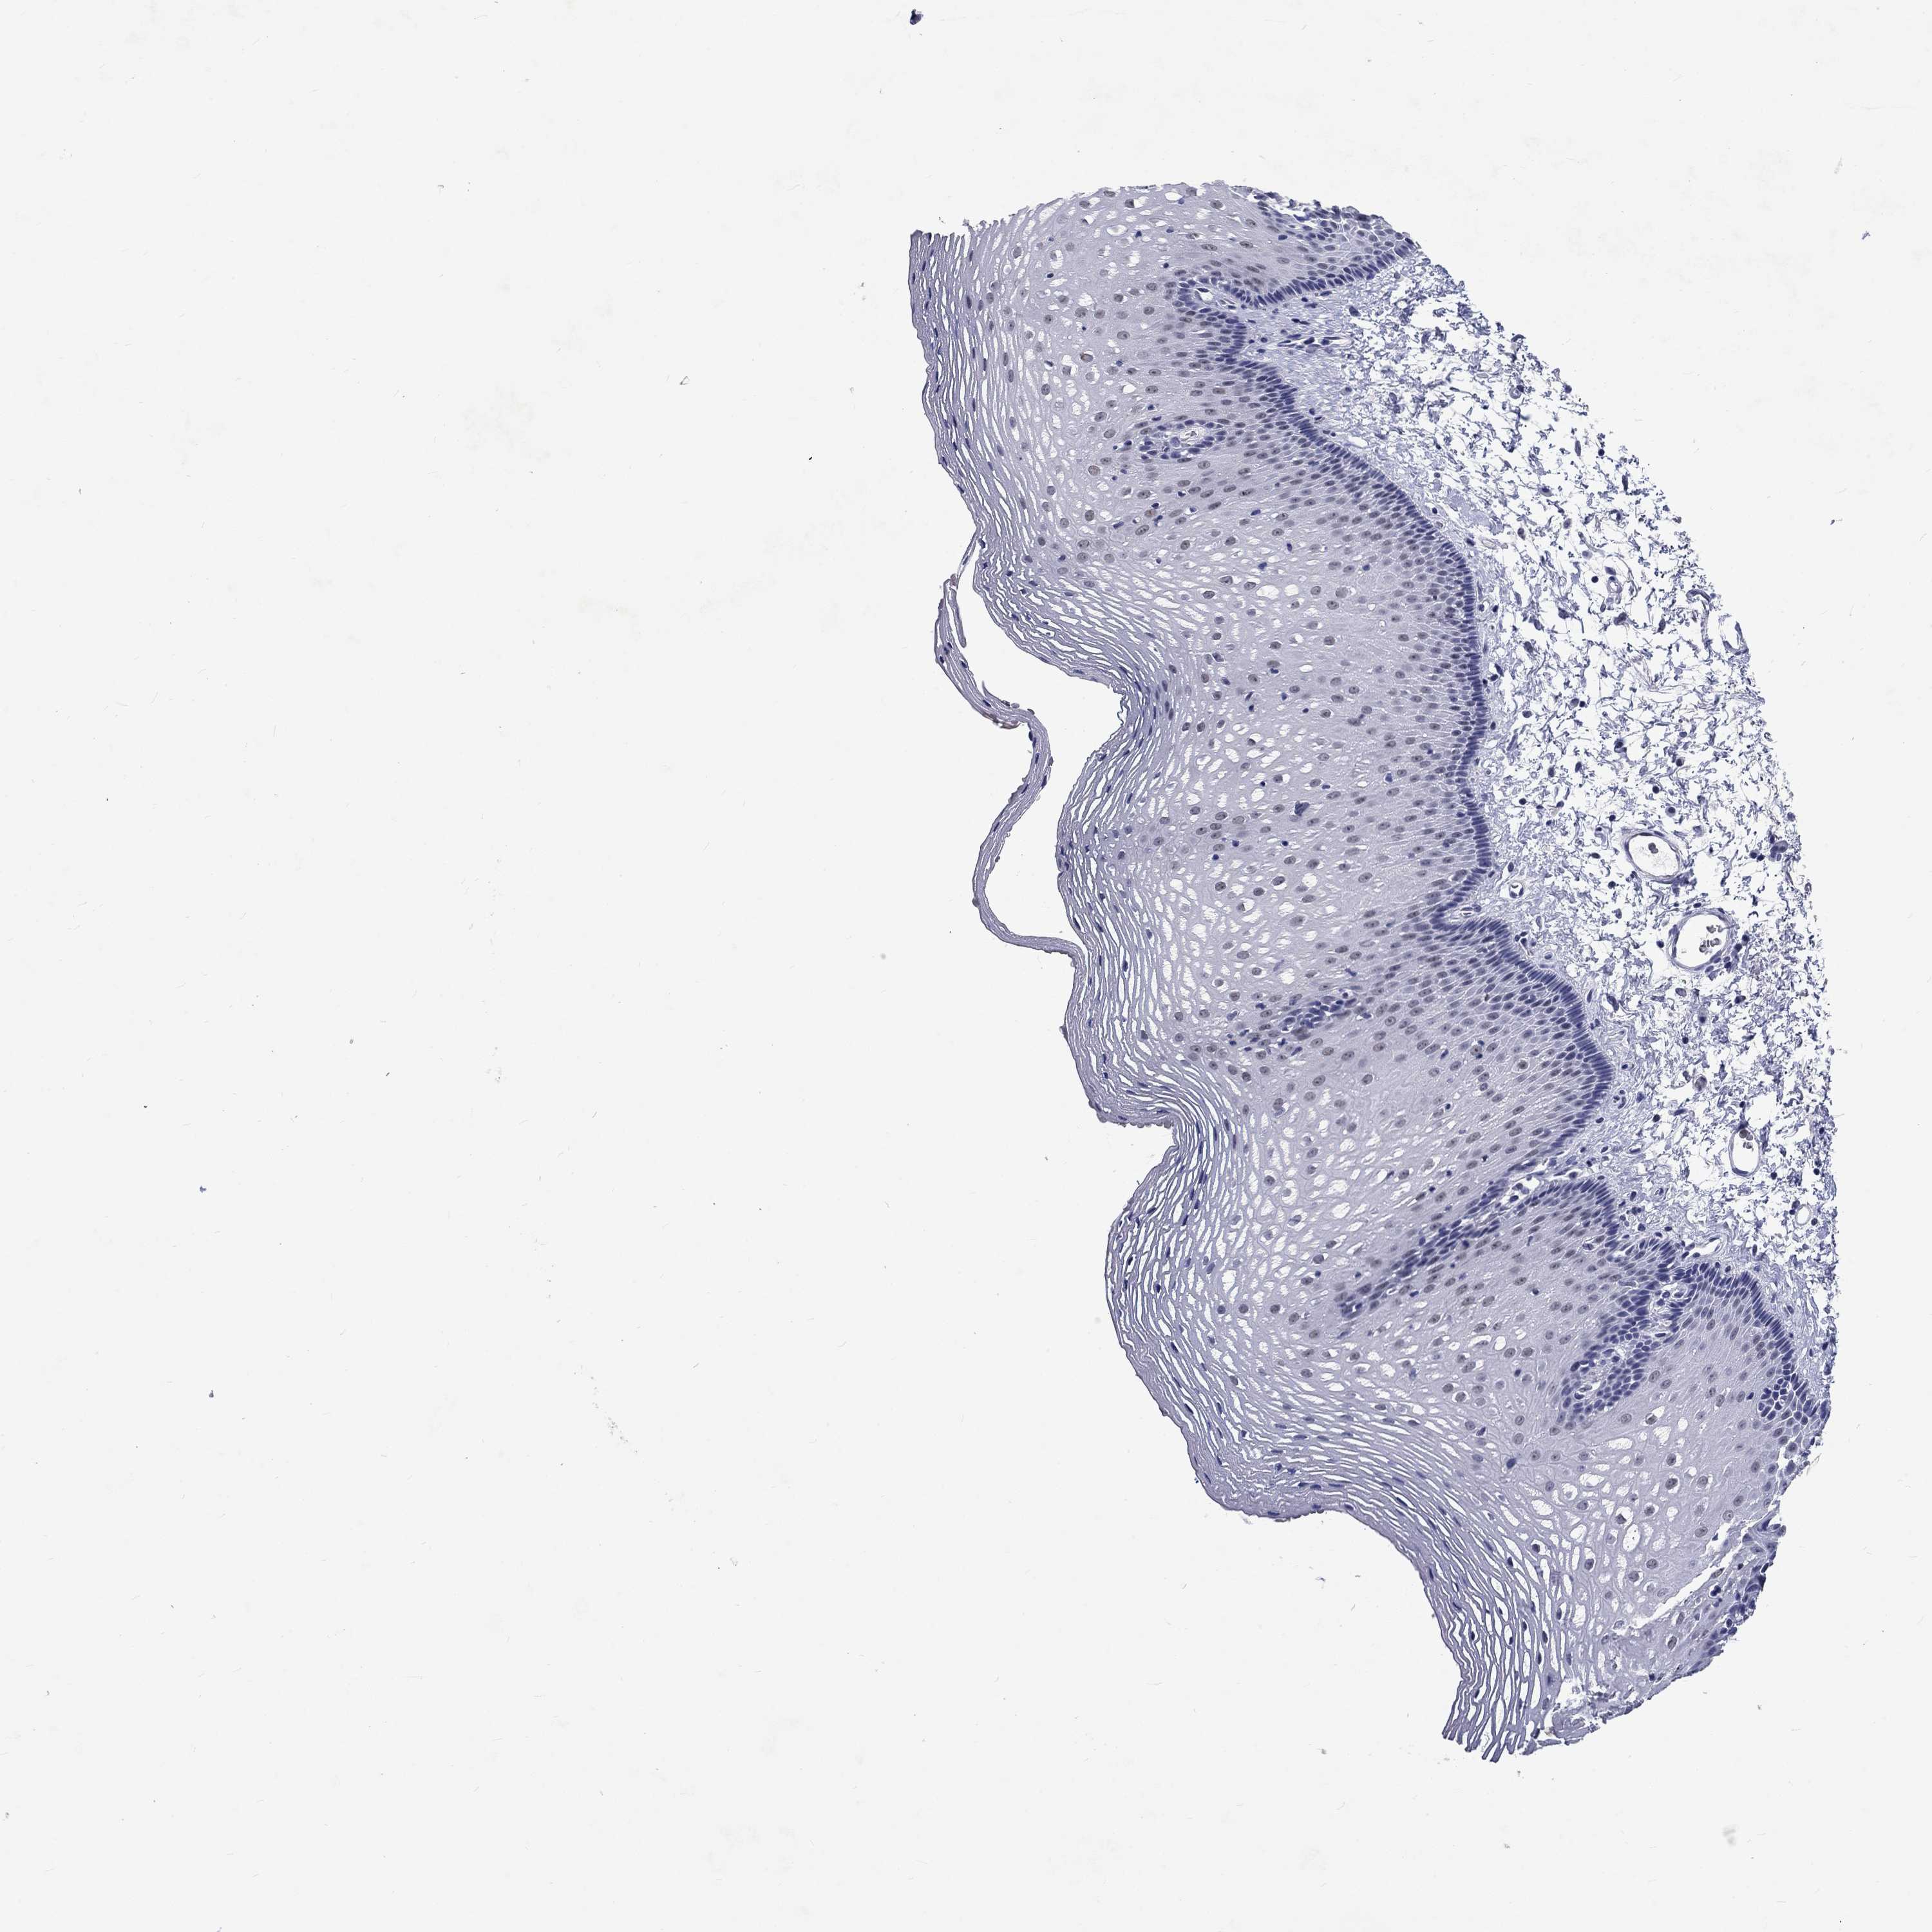

ESOPHAGUS - Antibody stainingi

Antibody staining in the annotated cell types in the current human tissue is reported as not detected, low, medium, or high, based on conventional immunohistochemistry profiling in selected tissues. This score is based on the combination of the staining intensity and fraction of stained cells.

Each image is clickable and will lead to virtual microscopy that enables deeper exploration of all samples and also displays staining intensity scores, fraction scores and subcellular localization as well as patient and tissue information for each sample.

Antibody HPA067773

Squamous epithelial cells Not detected